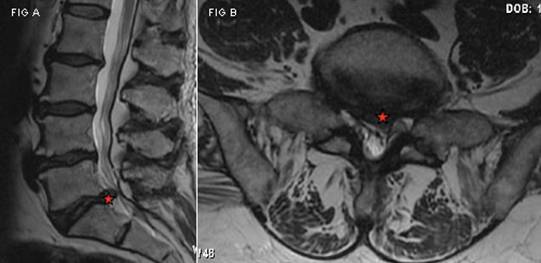

Диагностика данного заболевания основывается на анализе клинических проявлений и рентгенографических исследованиях. Обзорная рентгенография обычно не применяется, так как в прямой и боковой проекциях врач не может увидеть все патологические изменения в межпозвонковых дисках.

Наиболее четко выпячивание выявляется с помощью миелографии. Это рентгенографическое исследование спинного мозга, которое проводится путем введения рентгеноконтрастного вещества в спинномозговой канал. Процедура позволяет не только выявить протрузию, но и оценить степень повреждения межпозвонковых дисков.

Если у пациента отсутствуют признаки сдавливания мозга, но он испытывает сильные боли в пояснице, отдающие в ноги или руки, могут быть назначены магнитно-резонансная томография или компьютерная томография. Для более точной диагностики протрузии также используются дискография и пневмомиелография.

Дискография — это рентгеновское исследование межпозвоночного диска после введения специального контрастного вещества. Это позволяет врачу детально рассмотреть измененный диск и более точно оценить степень его поражения. Пневмомиелография включает введение небольшого количества воздуха в спинномозговой канал для проведения определенных исследований.